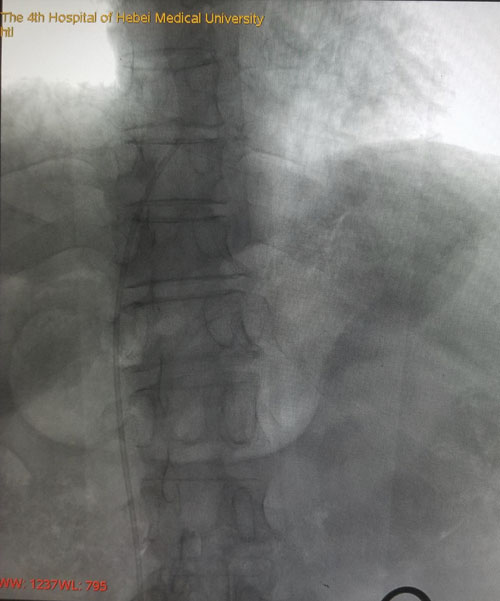

本例患者由于是双侧乳腺癌术后伴双侧颈部及左胸壁广泛转移而来我院就诊,难以建立常规输液通路。乳腺中心回天立主管医生通过查阅大量文献资料并结合既往手术经验,与宋振川主任反复商讨后制定了股静脉港的置入方案。手术当日,在超声科纪晓惠主任、放射科杨光主任的协助下,成功将导管送达下腔静脉与右心房结合部,港座埋置于右下腹壁皮下,完成了我省首例股静脉穿刺静脉港置入术。术后第一天患者恢复顺利,下床活动良好,静脉通路顺畅。

术后DSA评估导管尖端位置